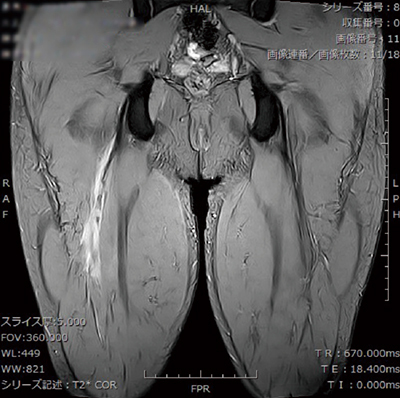

■症例2:右大腿二頭筋腱損傷

T2*強調画像,TR/TE=2900/75,スライス厚:5mm,FOV:360,マトリックス:320×256,DLR:Medium,VIVID:2,Mode:iRCM,撮像時間:2:16